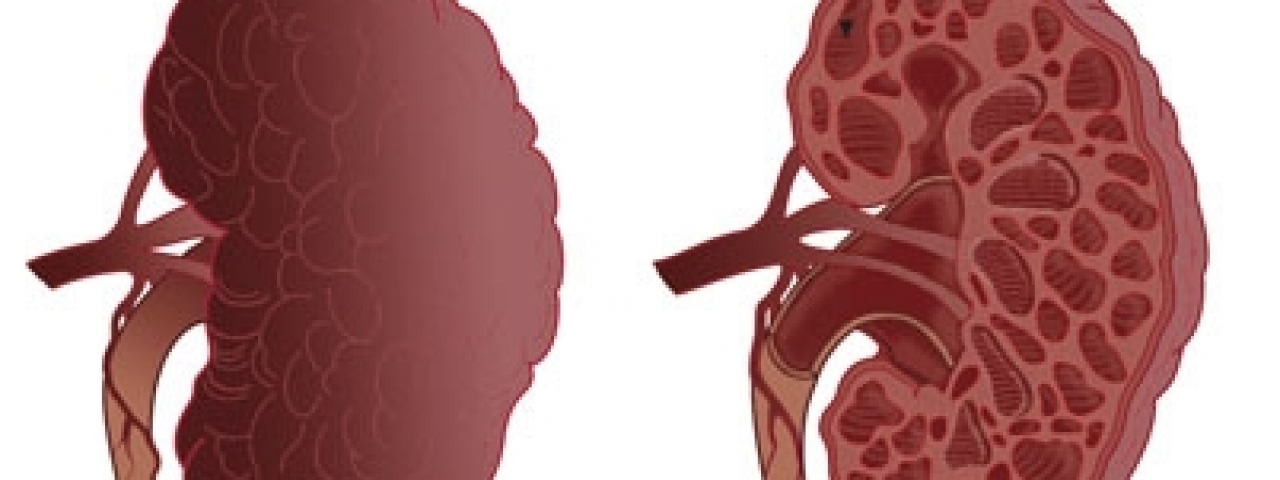

พบว่ามีถุงน้ำหรือซีสต์ (cyst) อยู่ในเนื้อไต ซีสต์จะงอกโตขึ้นเรื่อย ๆ จากเนฟรอนและขยายเบียดเนื้อไตที่ดีทำให้ไตเสื่อมและกลายเป็นโรคไตเรื้อรังมักพบในผู้ที่มีอายุตั้งแต่ ๓๐-๕๐ ปี อาการแสดงคือ มีอาการปวดหลัง บางครั้งคลำพบก้อนในท้อง มีการอักเสบติดเชื้อของทางเดินปัสสาวะบ่อย ๆ ปัสสาวะมีเลือดปน มีความดันโลหิตสูง โรคนี้ถ่ายทอดทางพันธุกรรมได้ดังนั้นจึงควรให้สมาชิกในครอบครัวตรวจปัสสาวะและถ่ายภาพเอกซเรย์ไตด้วย